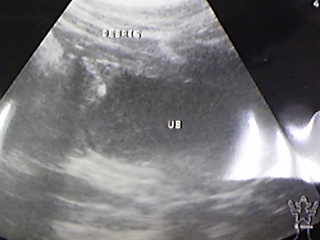

③ 11月16日

真ん中に白と黒の横線が3つあります

上黒=オシッコ

白中=ストラバイトの可能性

白下=腸